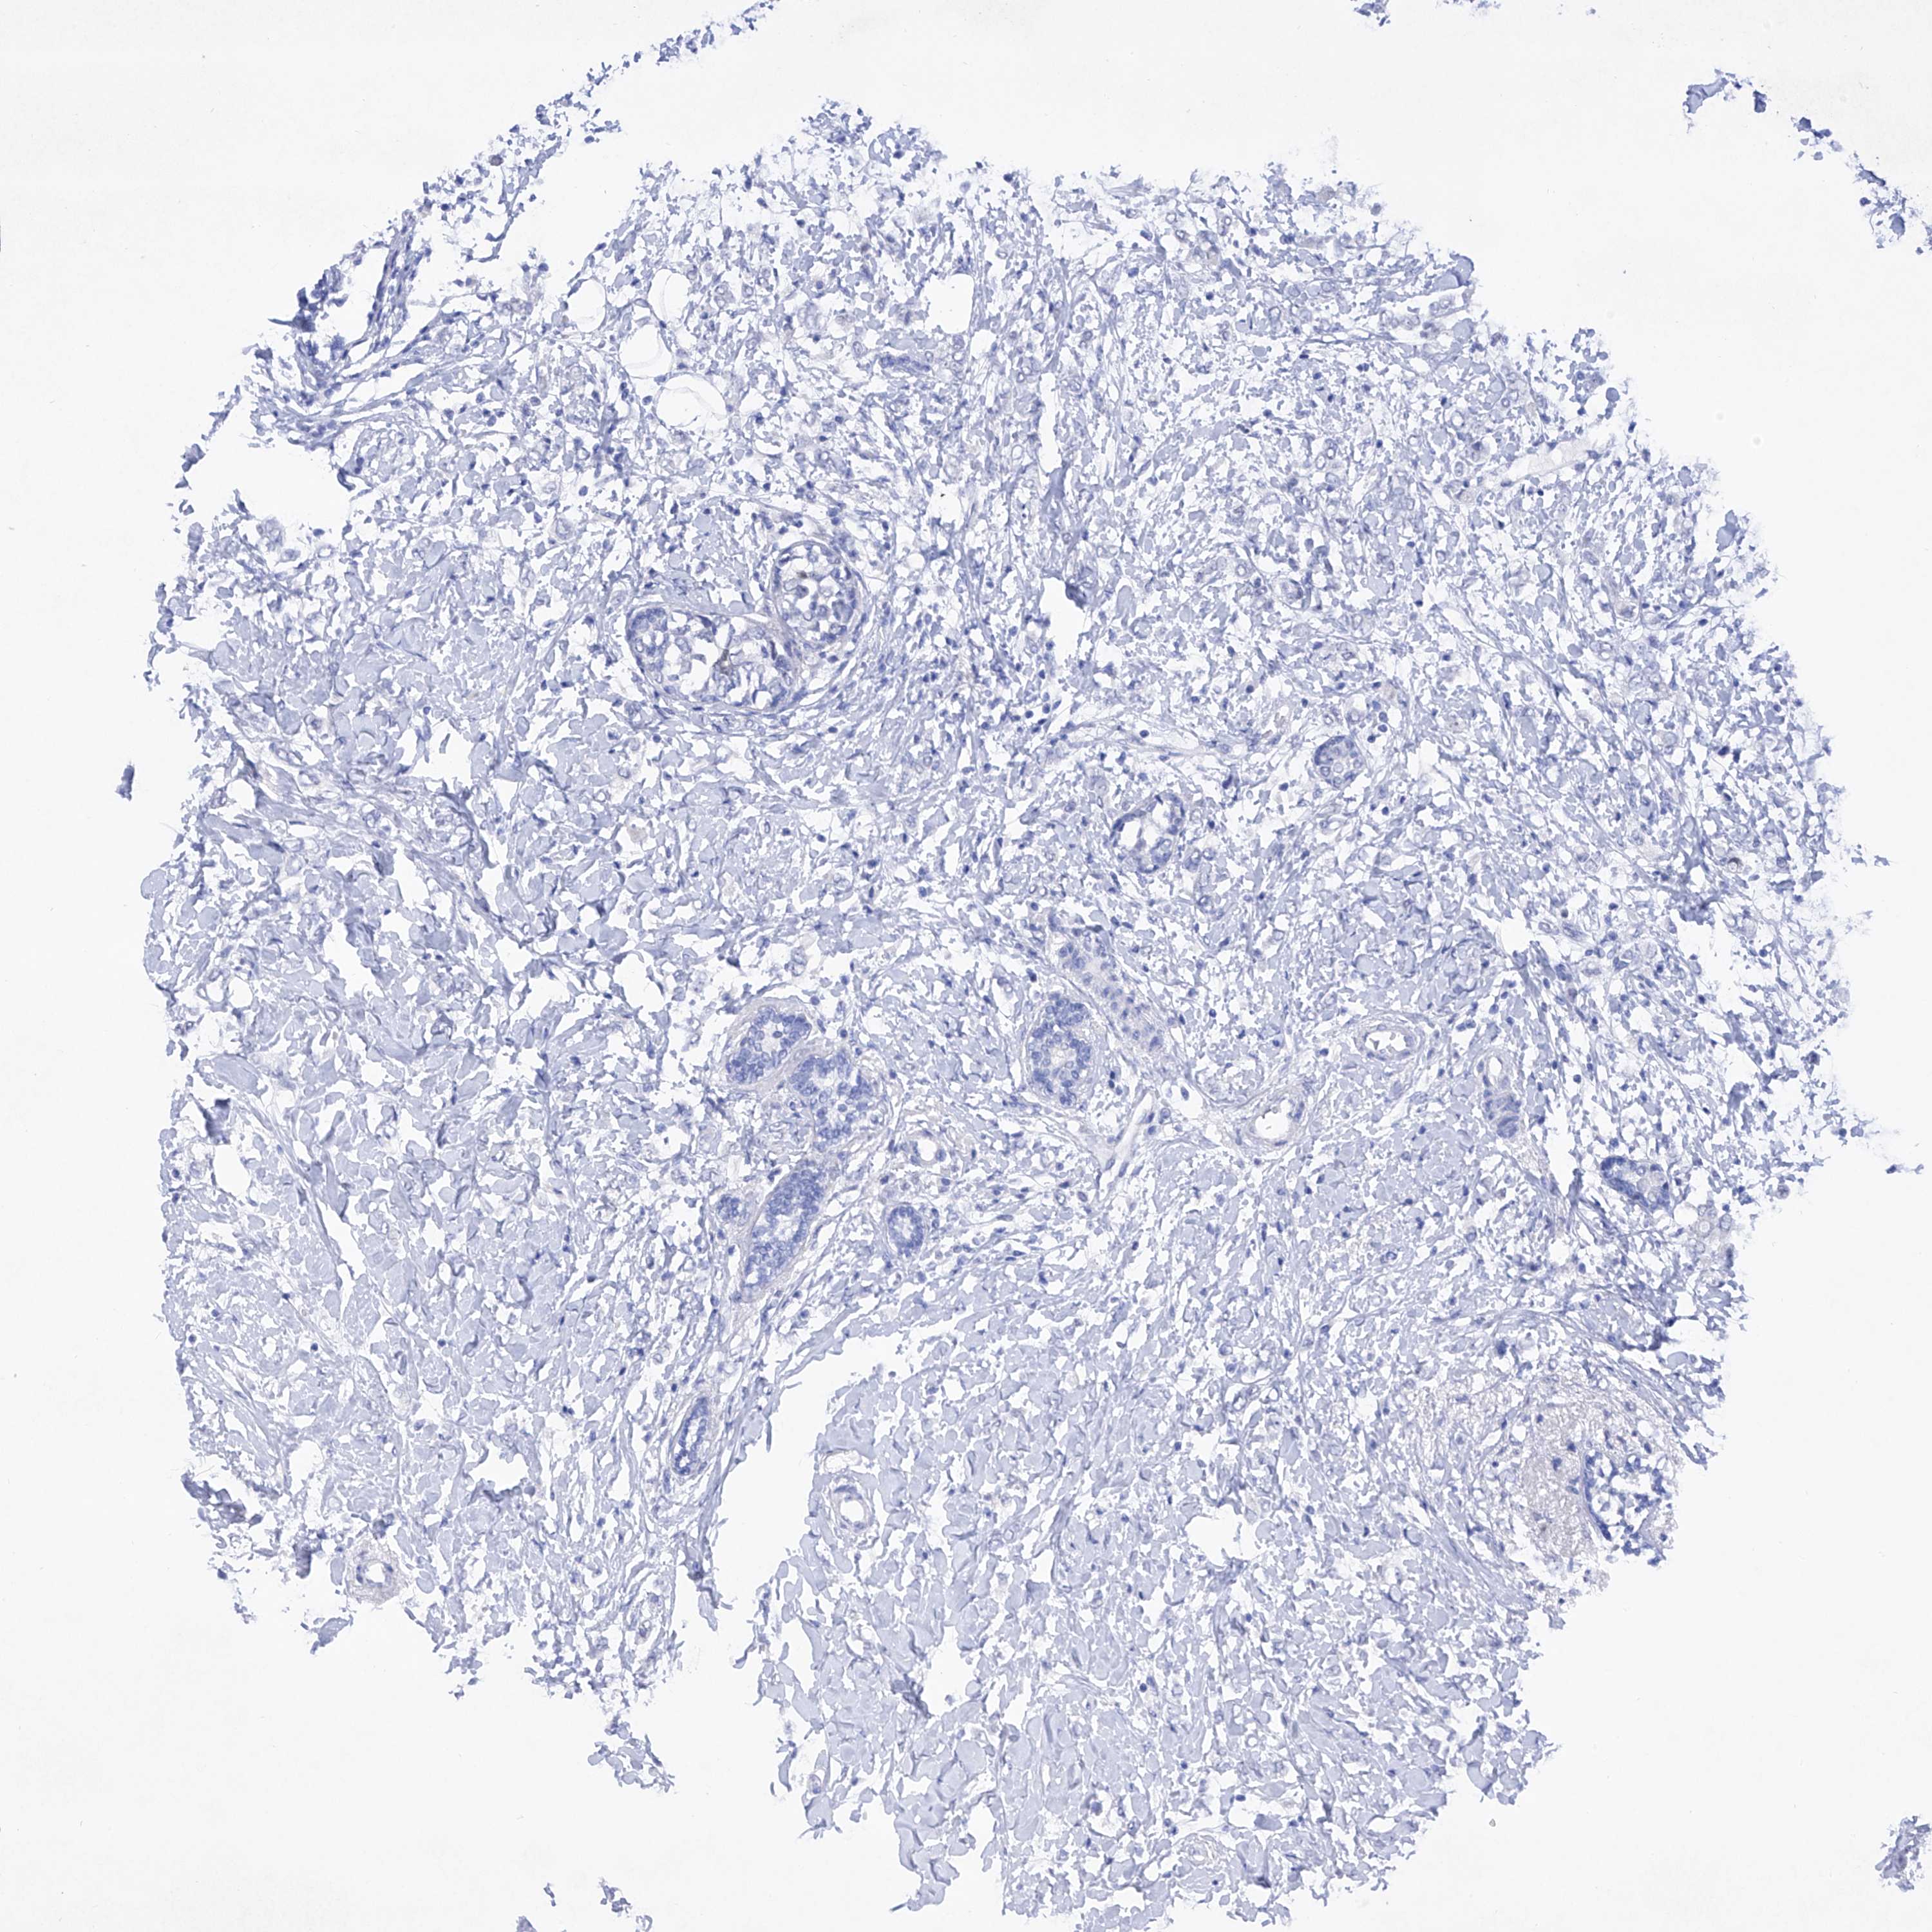

CANCER BREAST CANCER Show tissue menu

Breast cancer

Human cancer